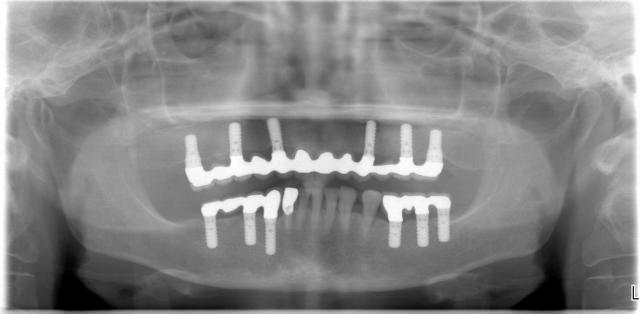

インプラント治療ができるといった方が2名いらしている。歯がまったくないときの

インプラント治療はいろいろなバリエーションが考えられる。4本の

インプラントで12本の歯を一気に回復するall on 4という手法であったり

アンキロスインプラントを使ってのsynconeによる即時荷重法であったり、さらに少ない2本もしくは4本の

インプラントで

義歯の支えとして使うオーバーデンチャーの方法である。

骨の厚みと高さ、骨の質が非常に重要であり即時荷重に向くのかをしっかりと検査しないといけないだろう。

CT検査とシムプラントのような

インプラントシュミレーションソフトなしには診断ができない。